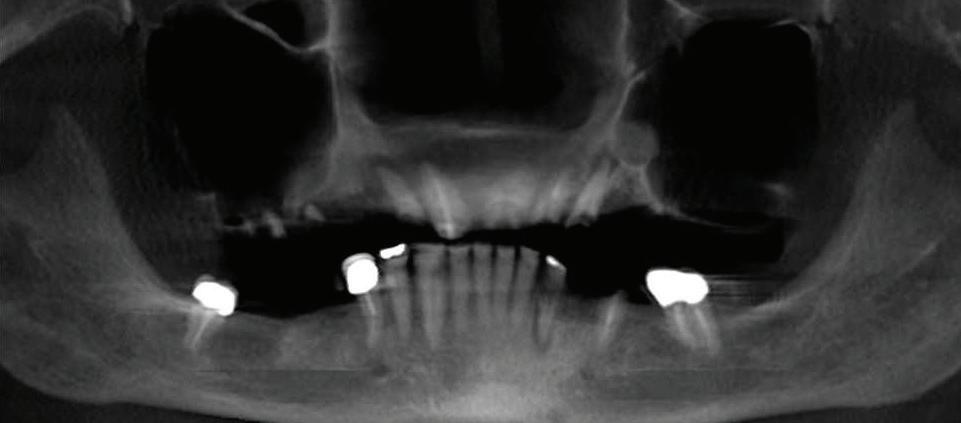

| What Is Cryotherapy? And How Can It Benefit You? | By Anthony T. Hardnett, DC 16 | All-On-Four Dental Implants | Submitted By Sivakumar Sreenivasan, DMD, MDS

Can just four implants replace all of the teeth on the top or the bottom of your mouth? Thanks to advances in dental implant technology, that answer is a resounding yes.

Tooth loss is extremely common among adults, especially as we age. Rather than living with the discomfort and hassles of dentures, many people are opting for what is called “all-onfour” dental implant restoration.

An implant is a small titanium screw

that fits inside your jawbone and replaces the root-part of a missing tooth. Minor surgery is required to insert the implants. Once the implant is in place, a crown is attached to give you a highly realisticlooking and functional prosthetic tooth. You do not need a dental implant for each and every one of your missing teeth. All you need is four precisely placed implants on the top of your mouth, and four on the bottom, to restore your full smile. That’s the beauty of the all-on-four. And because the implant is made of titanium, it has the unique ability to fuse to living bone and function as part of it. So eventually, the dental implant becomes part of the jawbone and serves as a strong, long-lasting foundation for your new teeth.

Besides ensuring that your implants are permanently fixed in place, this bone fusion has another important benefit: it prevents future bone loss in the jaw. This helps to maintain a more youthful facial structure – and better oral health. But perhaps the biggest